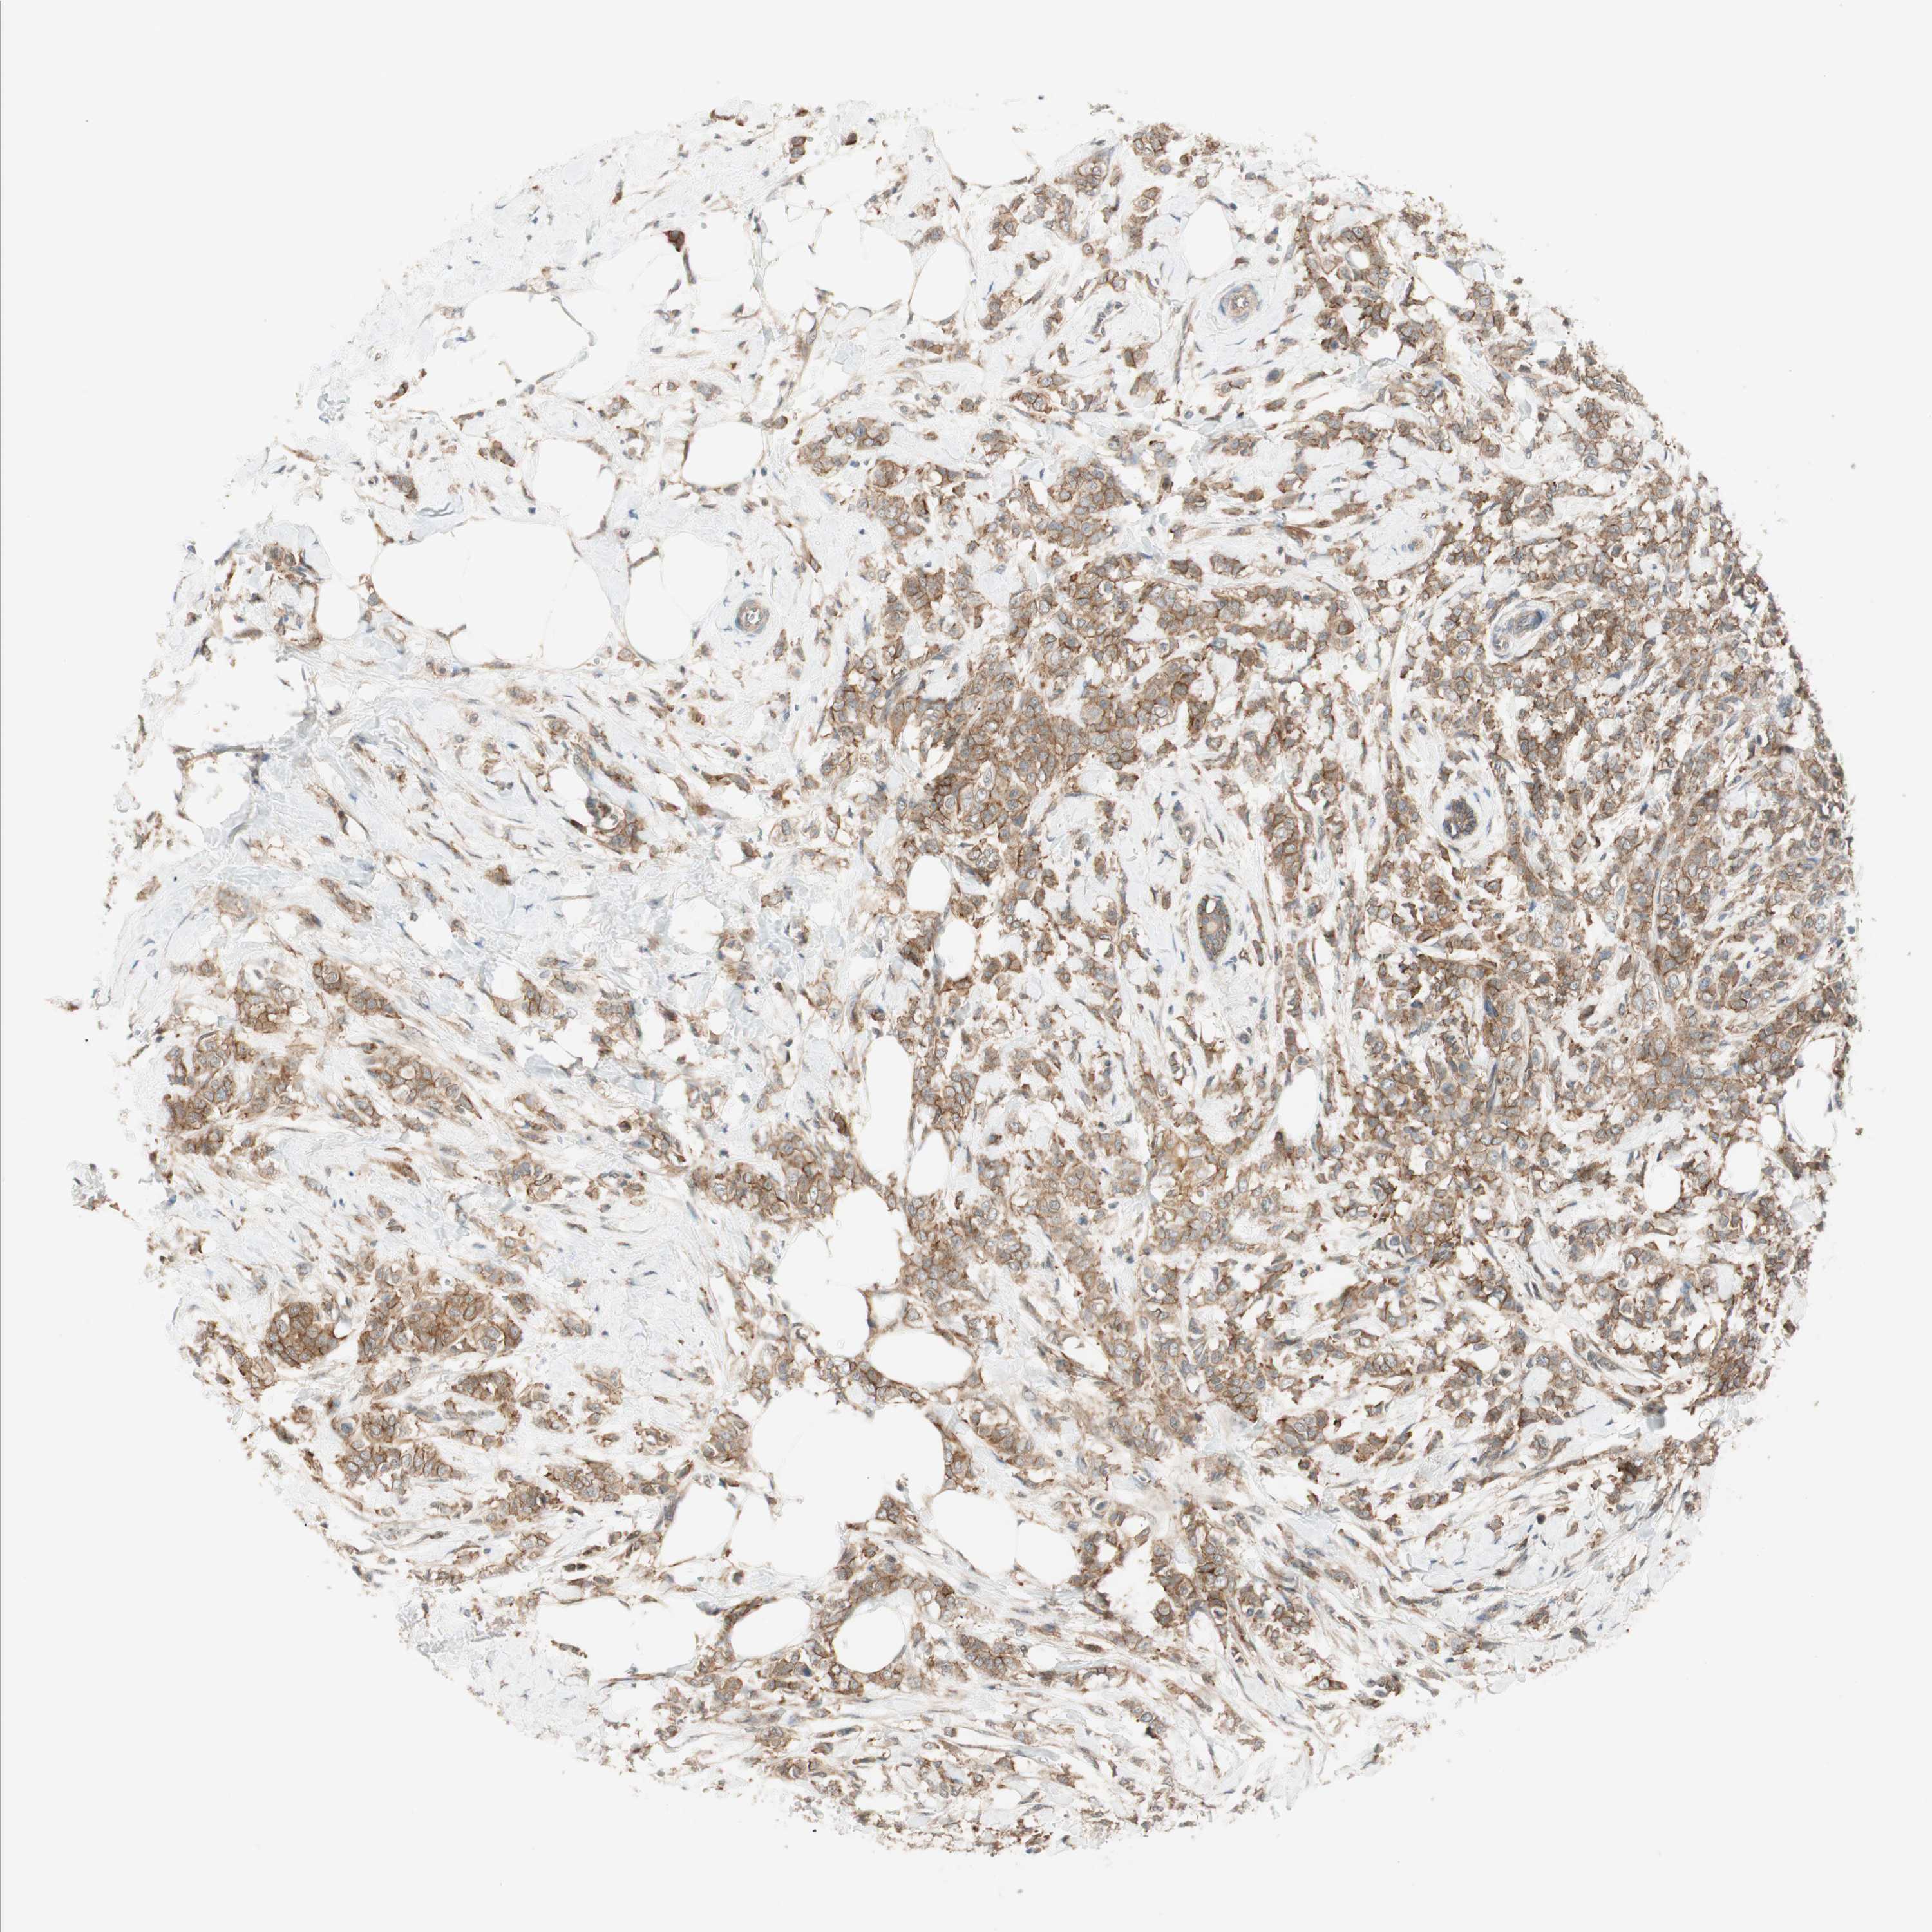

CANCER BREAST CANCER Show tissue menu

BRCA TCGA BRCA VALIDATION PROTEIN EXPRESSION

Breast cancer

Human cancer

Breast invasive carcinoma